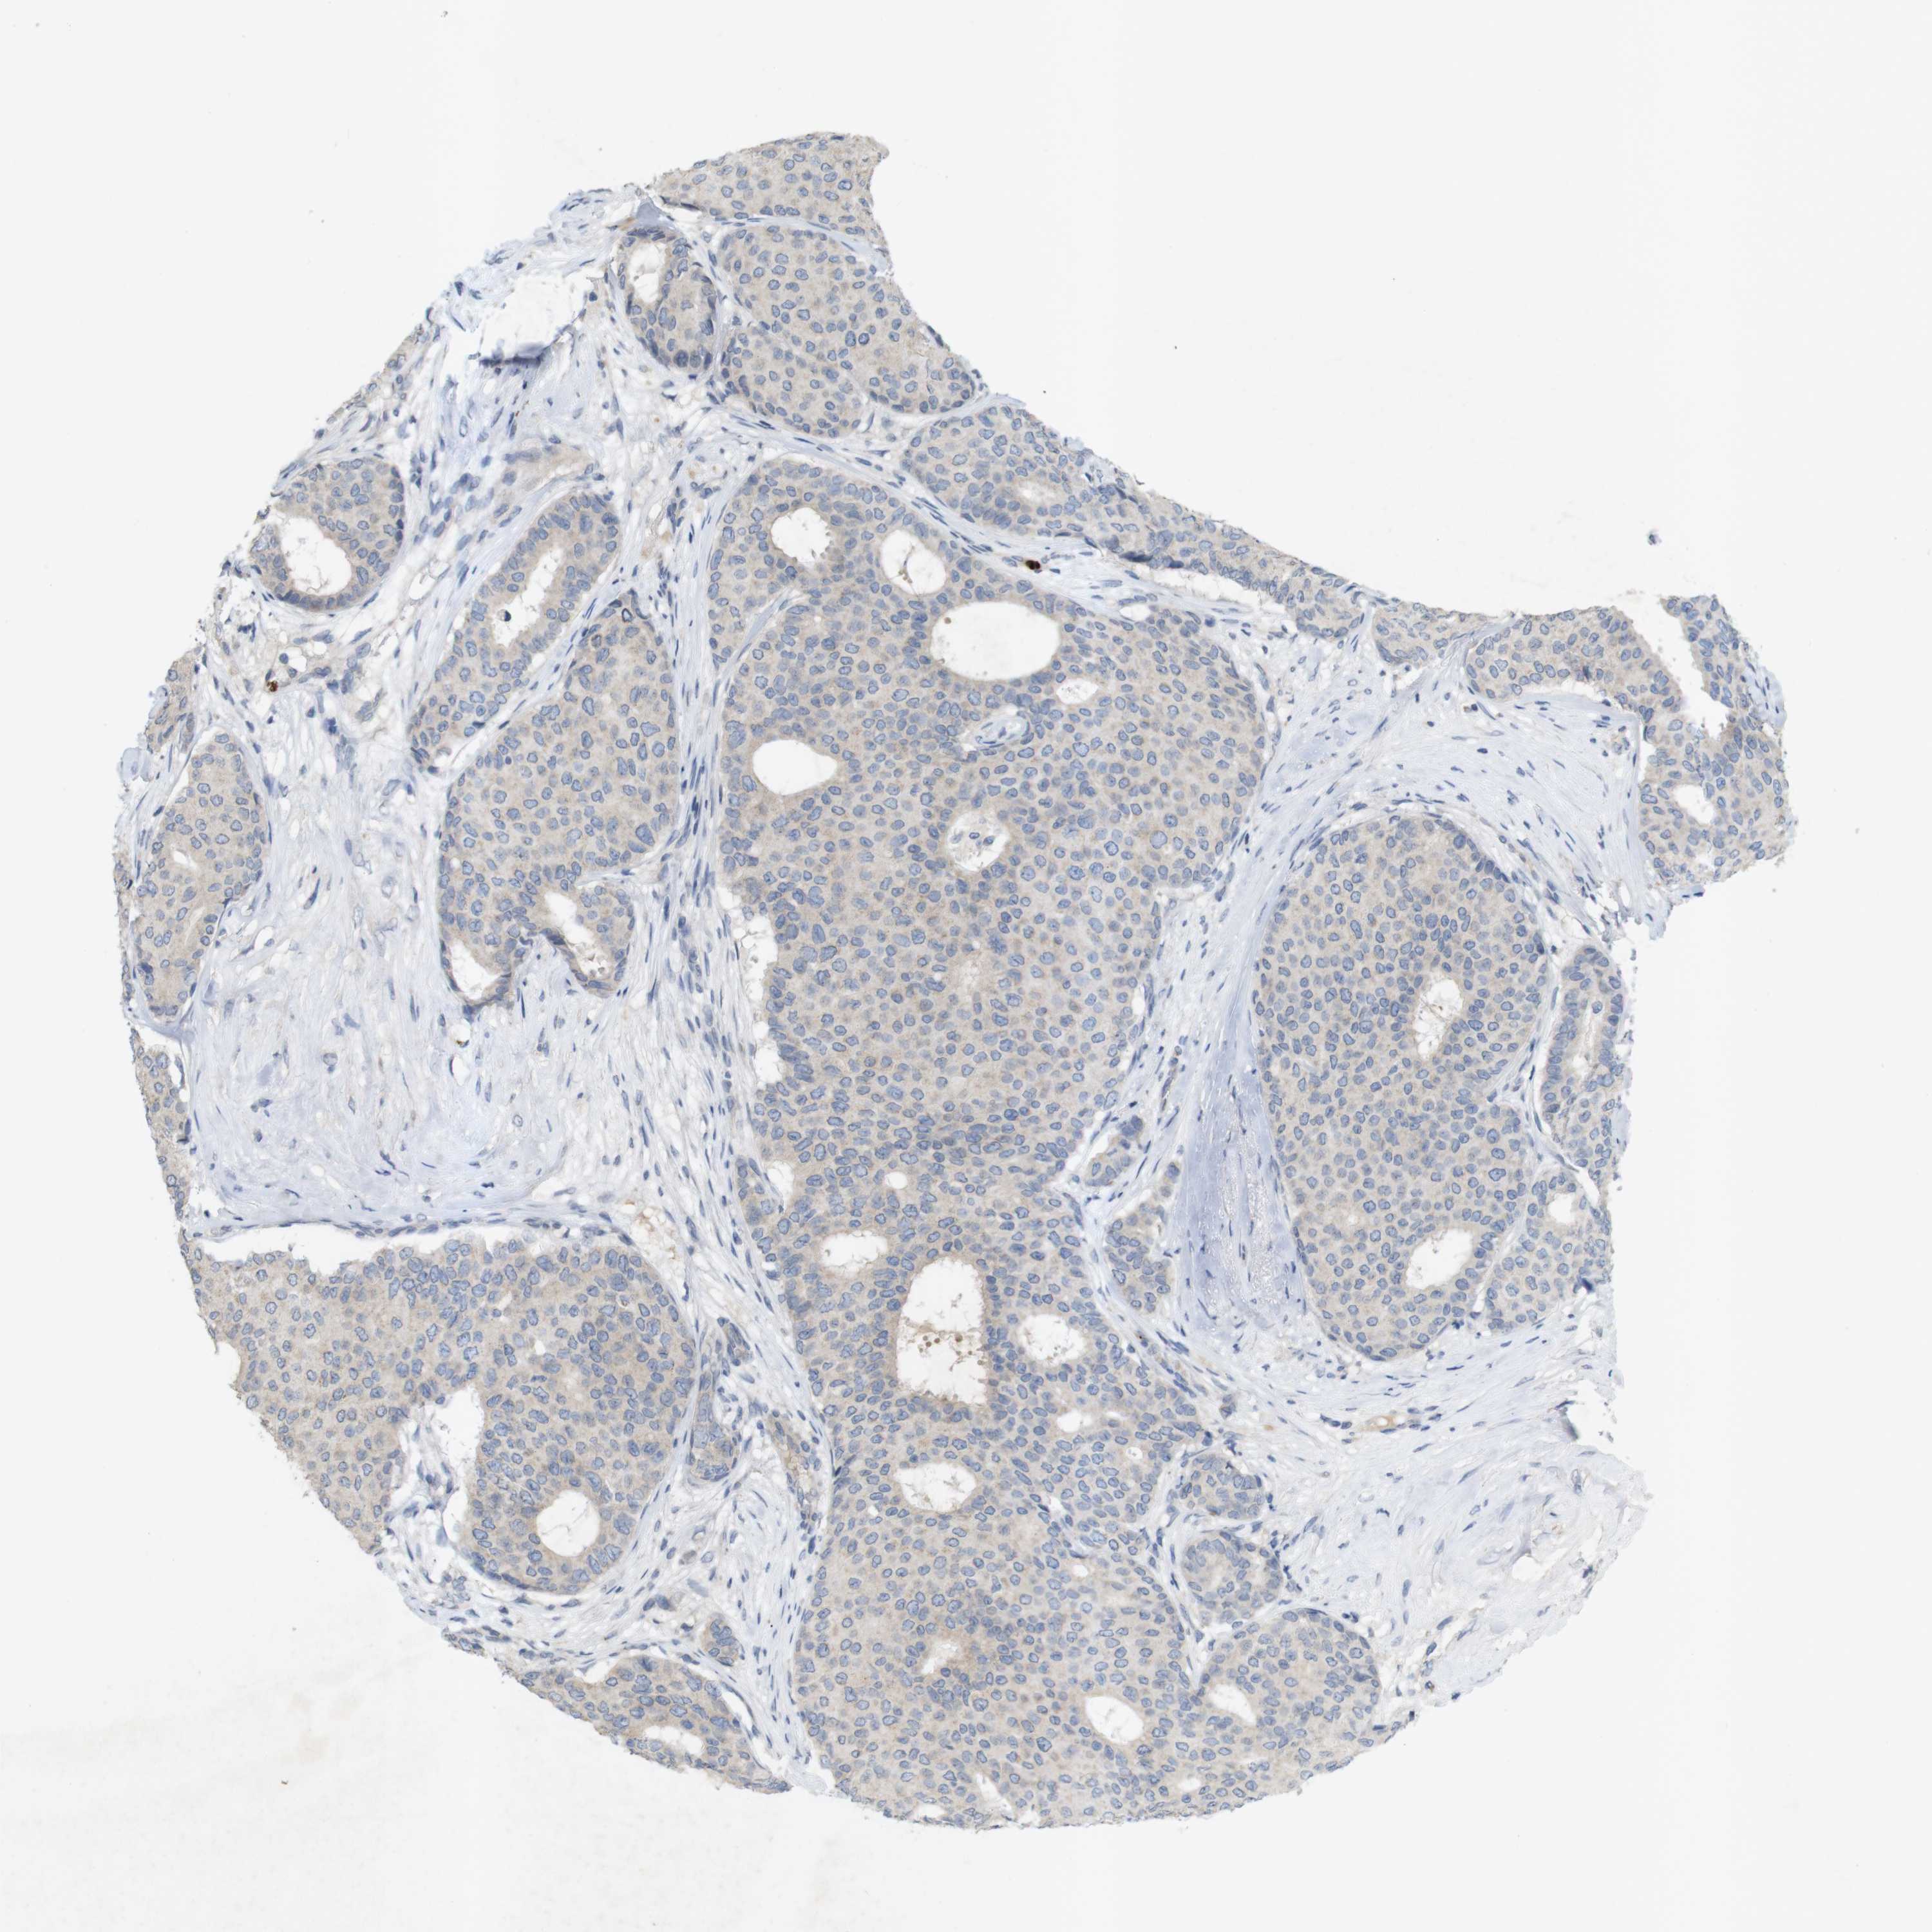

CANCER BREAST CANCER Show tissue menu

BRCA TCGA BRCA VALIDATION PROTEIN EXPRESSION